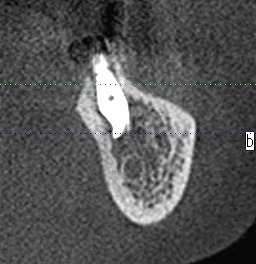

左下の7番部ではもっと埋入位置に制約が生じます

神経との距離も近くなります

インプラント自体を傾斜埋入せざるを得なくなります